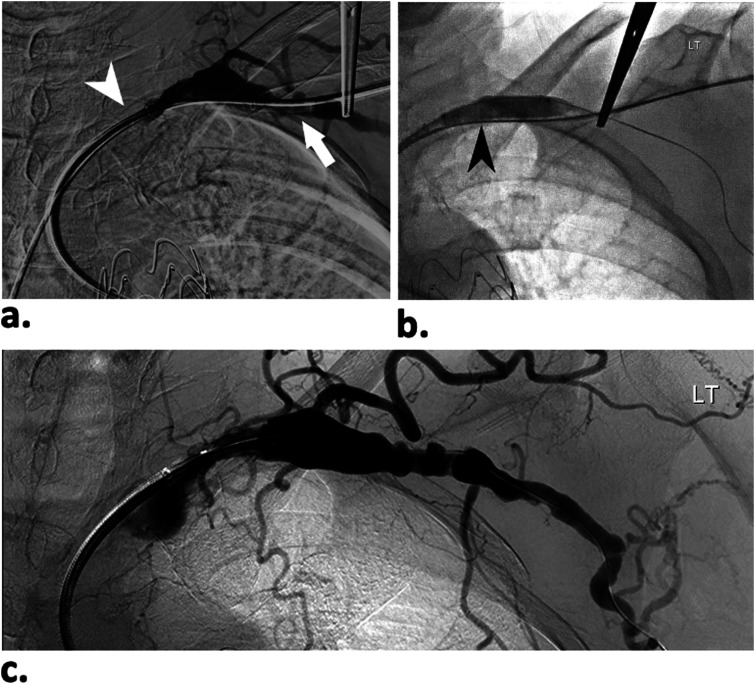

ObjectivesLimited knowledge exists regarding access site complication rates between trans-axillary and trans-brachial approaches with sheath sizes ≥6Fr. We retrospectively reviewed our institution experience with access site complications for percutaneous trans-axillary and trans-brachial arterial interventions using sheath sizes ranging from 6Fr to 10Fr.MethodsWe examined 67 endovascular interventions performed over 18 months, restricted to sheath sizes of 6Fr to 10Fr. Procedures utilizing trans-brachial (41 cases) and trans-axillary (26 cases) approaches under sonographic guidance were included. Cases involving hemodialysis accesses and those requiring surgical cut-down were excluded. The primary outcome measure was the occurrence of major access site complications (SIR grade-II/III) within 30 days, with data collected on hemostasis method, sheath size, and complications. Statistical analysis involved ANCOVA and Fisher's exact tests, with significance set at p < .05.ResultsSuccessful percutaneous arterial access was achieved in all cases using either approach (trans-axillary or trans-brachial). Closure devices were employed in all axillary punctures and in 71% of brachial punctures. Major access site complications occurred in 7 out of 41 cases (17%) in the trans-brachial group and in 4 out of 26 cases (15%) in the trans-axillary group. However, there was no statistically significant difference in complication rates between the two groups, regardless of access site or sheath size.ConclusionTrans-axillary access serves as a safe and effective upper limb access method for percutaneous endovascular procedures requiring sheath size of 7Fr or larger when compared to trans-brachial approach.

Abstract Image